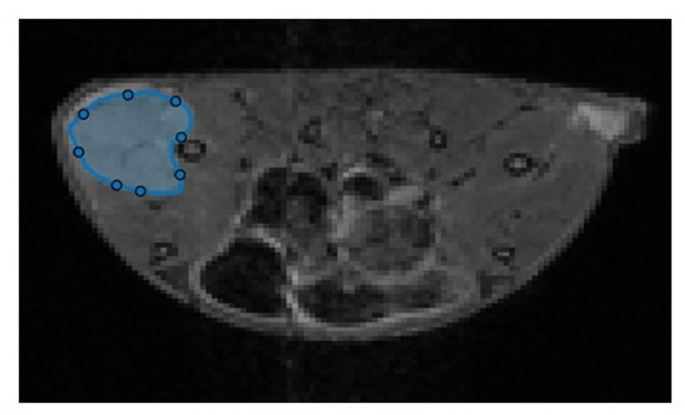

MATLAB code was created to obtain the signal values for each pixel and was used for image analysis in this study. The per-pixel signal values in the ADC map and CEST images were obtained by delineating the region of interest (ROI) around the tumor (Fig. 1). The ROI in the ADC and MTR maps at 1.2 ppm reflecting hydroxyl metabolite were unified, and signal values at similar locations were obtained. The tumors created in this study varied from individual to individual, and cavities were formed inside the tumors in some cases. In such cases, the cavity is avoided when it surrounds the ROI. In addition, MTR asymmetry was created from the MTR values within the tumor at 0–4.8 ppm in the CEST images acquired from each model group. This was used to assess the variation in MTR values.